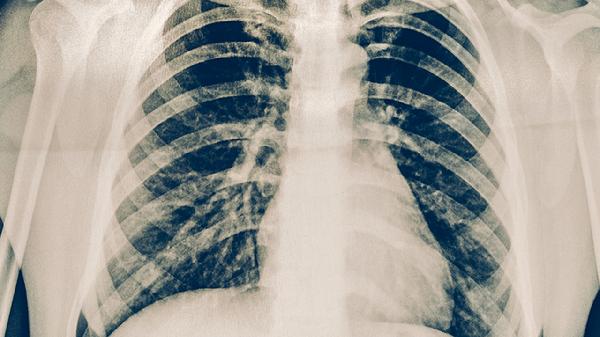

肺結節(jié)的病因是什么

肺結節(jié)可能由感染、良性腫瘤、惡性腫瘤、職業(yè)環(huán)境暴露、自身免疫性疾病等原因引起。

一、感染

感染是肺結節(jié)的常見原因,包括細菌感染、真菌感染結核感染等。細菌感染可能引起炎性假瘤,通常表現為咳嗽、咳痰等癥狀。真菌感染如曲霉菌感染可能導致肉芽腫性病變。結核感染形成的結核球在影像學上呈現為邊界清晰的結節(jié)。感染性結節(jié)的治療需針對病原體使用抗生素或抗結核藥物,例如異煙肼片、利福平膠囊、吡嗪酰胺片等抗結核藥物?;颊咝枰襻t(yī)囑完成規(guī)范療程,避免耐藥性產生。

二、良性腫瘤

良性腫瘤如肺錯構瘤、硬化性血管瘤等可能形成肺結節(jié)。肺錯構瘤由正常肺組織異?;旌蠘嫵?,通常生長緩慢且邊界清晰。硬化性血管瘤多見于女性,影像學顯示為孤立性結節(jié)。這些腫瘤一般無須特殊治療,但需要定期隨訪觀察變化。若結節(jié)增大或出現癥狀,可考慮手術切除。患者應避免吸煙等刺激因素,減少腫瘤進展風險。

三、惡性腫瘤

惡性腫瘤包括原發(fā)性肺癌或轉移性肺癌,是肺結節(jié)的重要病因。原發(fā)性肺癌如腺癌常在早期表現為磨玻璃結節(jié),伴隨胸痛或咯血。轉移性肺癌由其他器官腫瘤擴散所致,如乳腺癌肺轉移。治療需根據病理類型選擇手術、放療或化療。早期發(fā)現可通過胸腔鏡手術切除,晚期需結合靶向藥物治療?;颊咝枰ㄆ谶M行低劑量螺旋CT篩查,監(jiān)測結節(jié)動態(tài)。

四、職業(yè)環(huán)境暴露

長期接觸石棉、硅塵、煤塵等職業(yè)粉塵可能導致肺結節(jié)形成。石棉暴露可引起胸膜斑或間皮瘤,表現為胸膜下結節(jié)。硅塵暴露可能誘發(fā)矽肺,形成彌漫性小結節(jié)。這些結節(jié)通常伴隨呼吸困難或干咳。治療首要措施是脫離暴露環(huán)境,配合支氣管擴張劑如沙丁胺醇氣霧劑緩解癥狀。患者需加強職業(yè)防護,佩戴專用口罩減少粉塵吸入。

五、自身免疫性疾病

自身免疫性疾病如類風濕關節(jié)炎、結節(jié)病等可能引起肺結節(jié)。類風濕關節(jié)炎可導致類風濕結節(jié),多見于胸膜下區(qū)域。結節(jié)病特征為非干酪樣肉芽腫,常累及雙側肺門淋巴結。這些結節(jié)可能伴隨關節(jié)疼痛或皮膚病變。治療需使用免疫抑制劑如潑尼松片、甲氨蝶呤片控制原發(fā)病?;颊咝枰ㄆ诒O(jiān)測肺功能,避免感染誘發(fā)疾病活動。